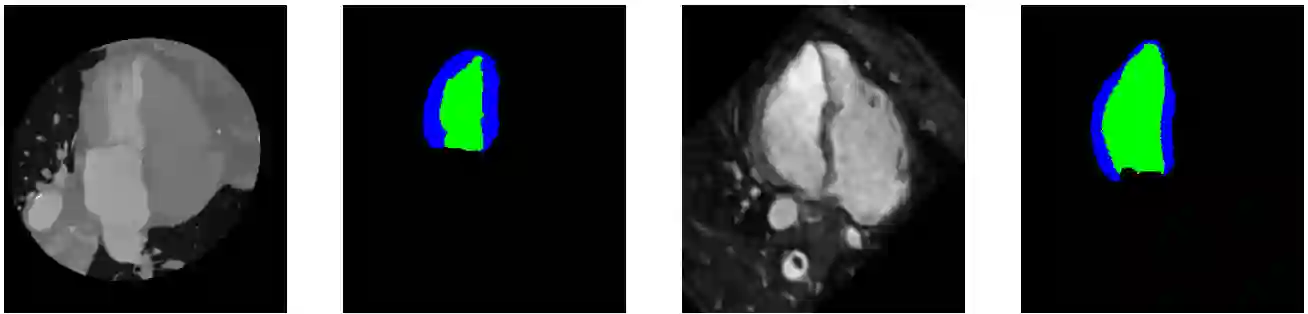

The presence of domain shift in medical imaging is a common issue, which can greatly impact the performance of segmentation models when dealing with unseen image domains. Adversarial-based deep learning models, such as Cycle-GAN, have become a common model for approaching unsupervised domain adaptation of medical images. These models however, have no ability to enforce the preservation of structures of interest when translating medical scans, which can lead to potentially poor results for unsupervised domain adaptation within the context of segmentation. This work introduces the Structure Preserving Cycle-GAN (SP Cycle-GAN), which promotes medical structure preservation during image translation through the enforcement of a segmentation loss term in the overall Cycle-GAN training process. We demonstrate the structure preserving capability of the SP Cycle-GAN both visually and through comparison of Dice score segmentation performance for the unsupervised domain adaptation models. The SP Cycle-GAN is able to outperform baseline approaches and standard Cycle-GAN domain adaptation for binary blood vessel segmentation in the STARE and DRIVE datasets, and multi-class Left Ventricle and Myocardium segmentation in the multi-modal MM-WHS dataset. SP Cycle-GAN achieved a state of the art Myocardium segmentation Dice score (DSC) of 0.7435 for the MR to CT MM-WHS domain adaptation problem, and excelled in nearly all categories for the MM-WHS dataset. SP Cycle-GAN also demonstrated a strong ability to preserve blood vessel structure in the DRIVE to STARE domain adaptation problem, achieving a 4% DSC increase over a default Cycle-GAN implementation.